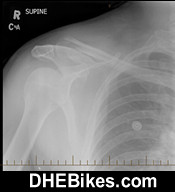

Shattered Left Scapula/ Shoulder:

Pic of DH Dave's shatterred left scapula that happened on a midnight film shoot off a stump jump in Langley, BC

Pic of DH Dave's shatterred left scapula that happened on a midnight film shoot off a stump jump in Langley, BC. The blue line is what the surgeon indicated as the shear line where the entire shoulder joint socket area of the scpaula sheared right off the scapula about 1 inch back from the rim of the shoulder socket. Apparently, scapula fractures make up less than 1% of all bone fractures so its quite rare. One of my riding mates and one of the star riders in my JUMP Bikefilm, Darren Leary also broke his left scapula a few years back now.

Shown above is Downhill Dave's badly broken left shoulder. Apparently the scapula was broken in 6 places and took a long time to heal. DH Dave also broke a few ribs at the same time and also shattered his downhill helmet in this crash...